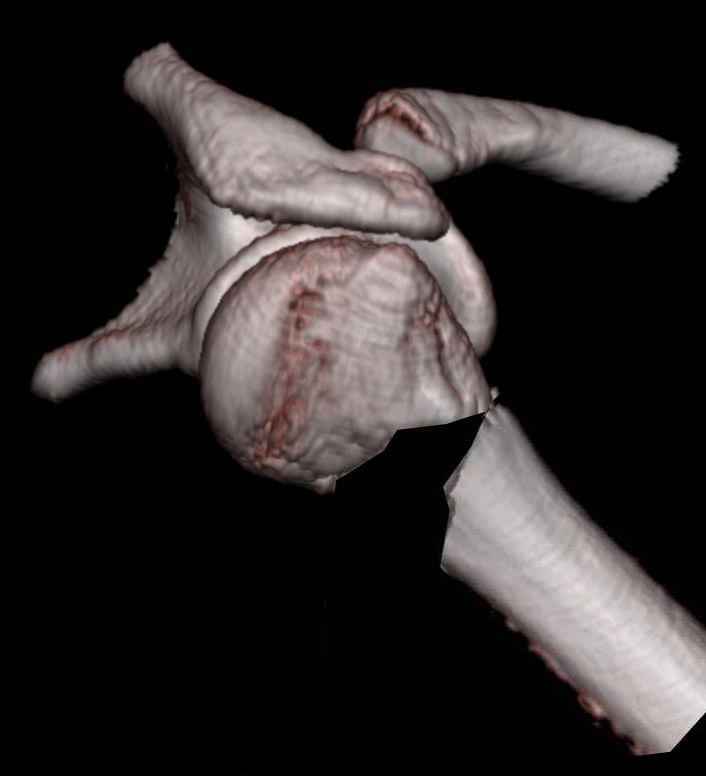

У нас это называется "по Мительману". КТ, да еще и возможность трехмерной реконструкции делает картину повреждения значительно более наглядной.

Эта "репозиция" сделана только на картинке, чтобы было видно, как основные фрагменты должны располагаться после восстановления взаимоотношений головки и диафиза. Понятно, такого диастаза не будет, поскольку есть внедрившаяся в головку медиальная стенка дистального отломка.

Ochen naglyadnaya demonstratsia pereloma - vashi radiologi nastoyaschie entuziasti ! kak udalos tebe ih ubedit delat CT s posleduyuschei 3D recon

dla takogo pereloma?

1.Mne kazhetsa, chto absolutno extrapolirovat post reduction reconstructiuy nedelnogo pereloma ne sovsem pravilno.

kak pravilo v eti sroki, pri manipulatii fragmentom za schet ligamentotaxisa proishodit desimpactiya i pustogo prostranstva mezhdu

fragmentami ne sozdaetsa kak eto pokazano na reconstructii.

Наш томограф вышел из строя, поэтому посылаем в другое усреждение, а там и аппарат поновее нашего, они всем на диск записывают и срезы вдоль-поперек-наискосок, и 3D.

e> 1.Mne kazhetsa, chto absolutno extrapolirovat post reduction reconstructiuy e> nedelnogo pereloma ne sovsem pravilno.

Последняя картинка сделана, чтобы более наглядно оценить тот угол, на который смещены отломки.